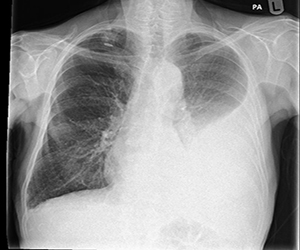

Pleural Effusion

Pleural effusion is accumulation of fluid around (not inside) the lungs. Most common causes include infections like tuberculosis, pneumonia; heart failure, kidney disease, cancer etc

- Chest X-ray